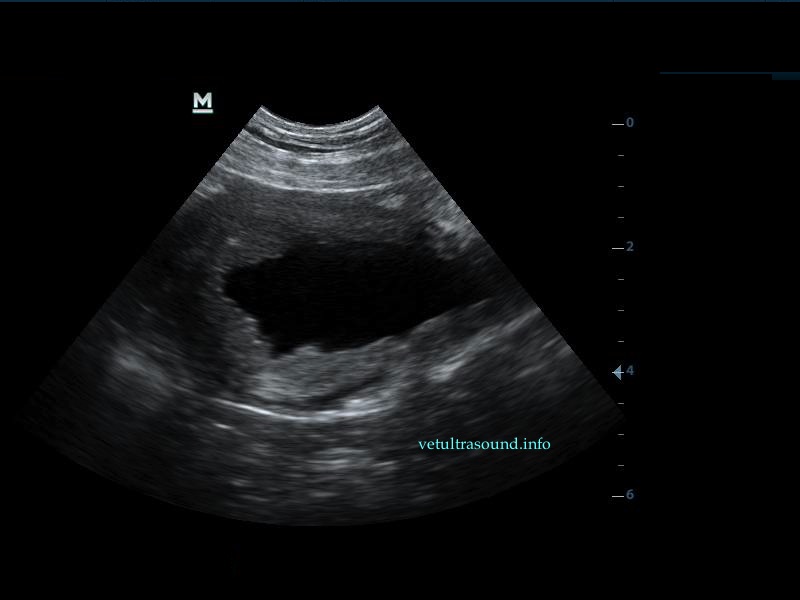

Η πάχυνση του τοιχώματος και η δοκίδωση του βλεννογόνου είναι εμφανής σε όλες τις εικόνες. Πολλές φορές οι λαγόνιοι λεμφαδένες μπορεί να είναι ήπια διογκωμένοι και να έχουν αντιδραστική ηχομορφολογία. Ο έλεγχος με έγχρωμο Doppler του τοιχώματος της άδειας κύστης μπορεί να μας δείξει ροή αίματος στα αγγεία της κύστης. Αντίθετα, είναι πιθανό, όσο η κύστη γεμίζει με ούρο η ροή αίματος να μην είναι ορατή με το Doppler. Αυτό συμβαίνει συχνά στη χρόνια βακτηριακή κυστίτιδα λόγω της ίνωσης του τοιχώματος της ουροδόχου και αυτή είναι μία από τις αιτίες της μη ανταπόκρισης στη θεραπεία. Η συγκεκριμένη παθοφυσιολογία έχει μελετηθεί στον άνθρωπο με την βοήθεια ενδοσκοπικού υπερήχου.

The increase of thickness of the urinary bladder wall and the striation of the mucosa is evident. Inguinal lymphnodes are usually prominent and mildly enlarged. Colour Doppler may reveal the blood flow of the mucosa of the empty urinary bladder, whereas the blood flow in a full bladder appears decreased. This could be because of the fibrosis of the urinary bladder wall and could explain why sometimes chronic conditions like these do not respond well to antibiotics. This pathophysiology has been studied in humans with the use of endoscopic ultrasound.